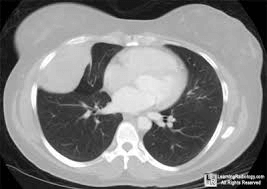

Με τον όρο οζίδιο ή όζος, εννοούμε ένα υπέρπυκνο ιστό σε σχέση με το υπόλοιπο πνευμονικό παρέγχυμα το οποίο εντοπίζουμε με κάποια απεικονιστική εξέταση όπως ακτινογραφία ή αξονική τομογραφία θώρακος.

Είναι πολύ σημαντικό να επιβεβαιωθεί αν ένα οζίδιο είναι καλοήθες ή είναι σε πολύ αρχικό στάδιο κακοήθεια.